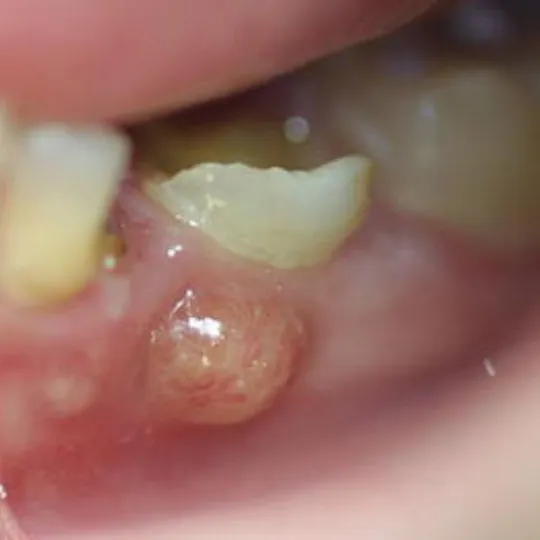

Inflammation of the gums or a tooth abscess

Once the bacteria reach your pulp, they can spread deeper into your gums or jawbone. Your gums may begin to swell, and you may notice a pimple-like bump on your gums.